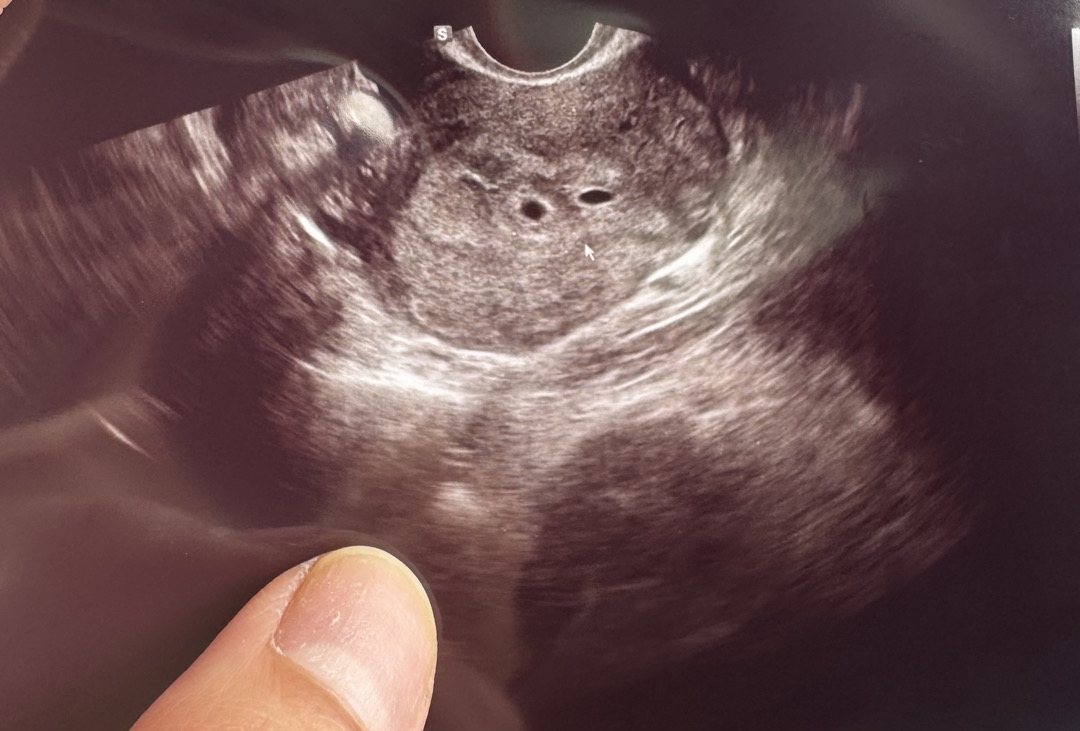

3일배양 17일차에 초음파 한거에요! 피검사는 1만이상 나왔다고 하셨고 크기는 4주3일정도 됐고, 착상은 잘됐다고 하시는데 보기에 어떤가요?ㅠㅠ

아그래요??볼줄을 너무 몰라서 ㅠㅠ 감사합니다😭

하나가 좀 짜부된것 같아서 이게 되도 걱정이 산넘어 산이네요🥹 감사합니다!!!